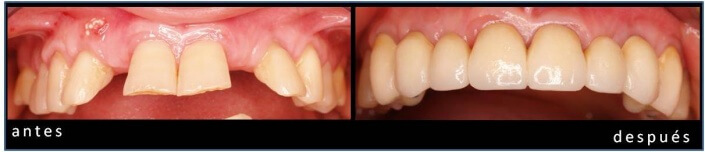

REHABILITACION MAXILAR SUPERIOR